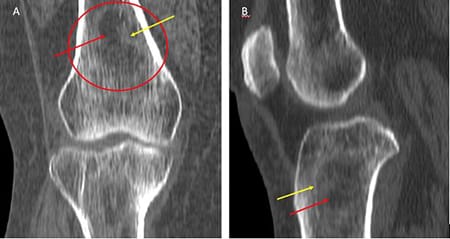

Tomografia computadorizada (TC) nos planos coronal (A) e sagital (B) evidenciando lesão heterogênea com centro radiolucente (setas vermelhas) e halo esclerótico (seta amarela).